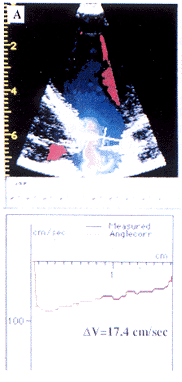

1.主动脉瓣口血流速度分布:在每帧彩色血流图中对主动脉瓣口血流速度分布进行分析。利用计算机及其相关软件,在主动脉瓣口水平画一条直线,即可获得沿该直线上的70个血流速度值及血流速度分布曲线。根据主动脉瓣口脉冲多普勒频谱,选择左室射血加速期中点、射血峰值点和射血减速期中点三个时间点,对整个射血期主动脉瓣口血流速度分布曲线的动态变化进行分析(图1)。血流速度分布曲线扭曲程度的定量指标为主动脉瓣口直径中点两侧(前半部与后半部)的平均血流速度之差(ΔV,cm/s)。

白线指示主动脉瓣口水平。坐标中,横轴代表主动脉瓣口直径(cm),方向为从前壁到后壁。纵坐标代表血流速度(cm/s)。

LA=左心房;LV=左心室;AO=主动脉。ΔV=主动脉瓣口直径中点两侧(前半部与后半部)的平均血流速度之差

图1 左室射血加速期中点(A),射血峰值点(B)和射血减速期中点(C)时左室流出道内彩色多普勒血流及相应的主动脉瓣口血流速度分布曲线